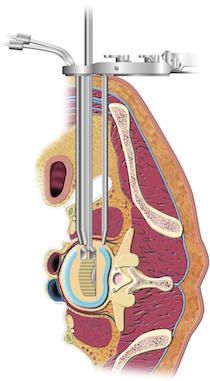

La intervención se realiza con el paciente anestesiado y colocado de lado, y con una pequeña incisión en el costado a la altura del espacio que queremos intervenir, y con la ayuda del aparato de Rayos X se localiza el espacio a intervenir (Fig 2).

Se realiza disección roma, separación de las estructuras con torundas, y especial cuidado, para evitar lesionar estructuras.

Se deja el peritoneo por delante de la columna vertebral. El psoas queda en la parte lateral de la columna, y hay que entrar entre sus fibras, intentado separarlo hacia posterior.

Posteriormente con la ayuda de un separador especial (Fig 3) y de instrumentos específicos, se reseca el disco intervertebral con el fin de colocar cajas rellenas de injerto en lugar de los discos que se han quitado y conseguir con esto diferentes funciones una separación de las vertebrales y por tanto un aumento del canal espinal y de los forámenes por los que salen las estructuras nerviosas, con lo que se consigue una descompresión de los elementos nerviosos (descompresión indirecta) (Fig 4).